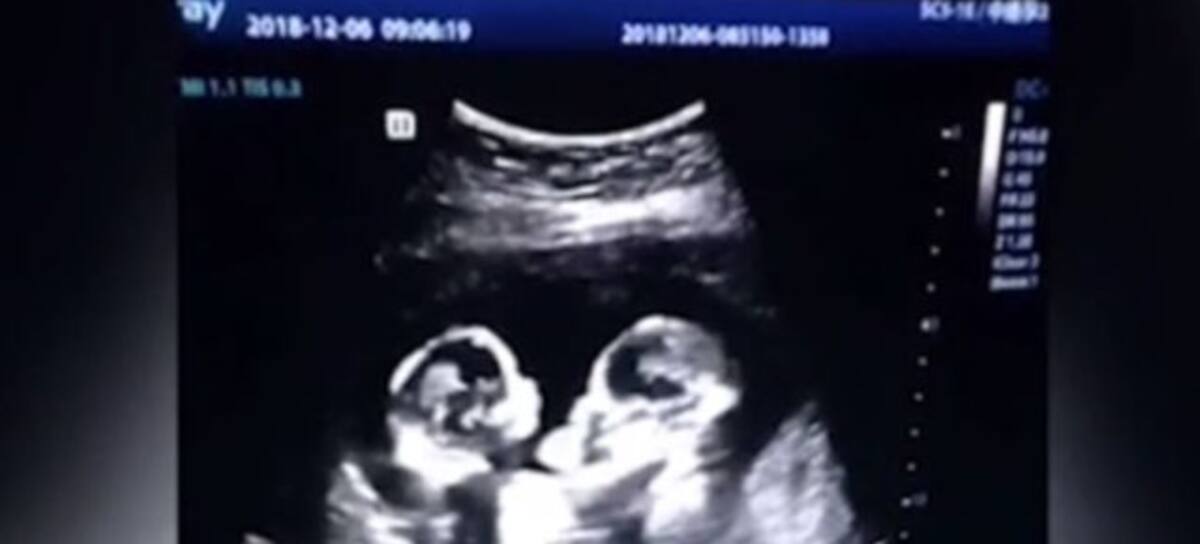

El siguiente clip es de un ultrasonido y muestra como aparentemente dos gemelas se están peleando en el útero de su mami.

En el clip se aprecia como las gemelas se encuentran una frente a la otra y se golpean entre si, según informa el portal Daily Mail las gemelitas nacieron sanas y salvas 4 meses después de la pequeña riña.